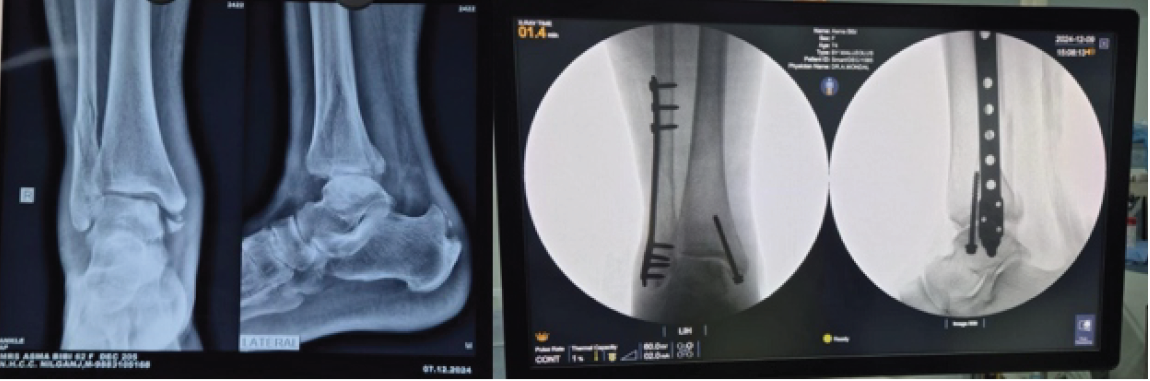

The incision for MIPO was significantly smaller than for ORIF (Fig. 7). A representative case of MIPO fixation is shown in pre- and immediate post-operative radiographs (Fig. 8).

Figure 8: Pre-operative and immediate post-operative in a patient where minimally invasive percutaneous plate osteosynthesis fixation was done.